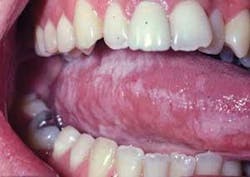

Perioral and intraoral characteristics: HL is asymptomatic unless there is a candida infection in conjunction with HL, causing the characteristic burning sensation associated with candidiasis. The hygienist or dentist may be the first individual to notice the clinical signs related to suppressed immune function. The nonpainful, white, and corrugated/shaggy plaque appear as accentuated folds on the lateral borders of the tongue and are very characteristic of HL. The lesions are usually bilateral, but may be unilateral as well (see Figure 2).